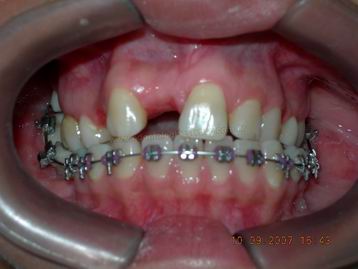

Adição de um elemendo provisório após instalação do aparelho fixo na maxila